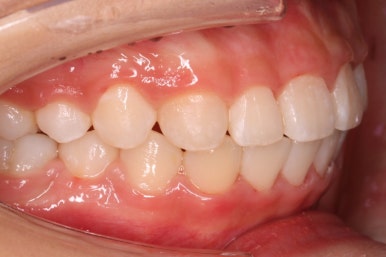

부산치아교정잘하는곳 처음 오셨을 때의 입안 모습입니다.

맨 우측 밑에 사진을 보시면 이가 하나 더 나와야 할 자리에(화살표) 앞뒤로 치아가 쓰러지면서 자리를 거의 없애버렸습니다.

따라서 이가 나올래야 나올 수가 없는 상태였습니다.

왼쪽 맨 위 사진을 보시면 아래 치열의 중앙이 한 쪽으로 쏠린 것을 알 수 있는데요. 역시 치아가 나올 자리가 없어지면서 치열이 쏠러버렸다는 것을 알 수 있습니다.